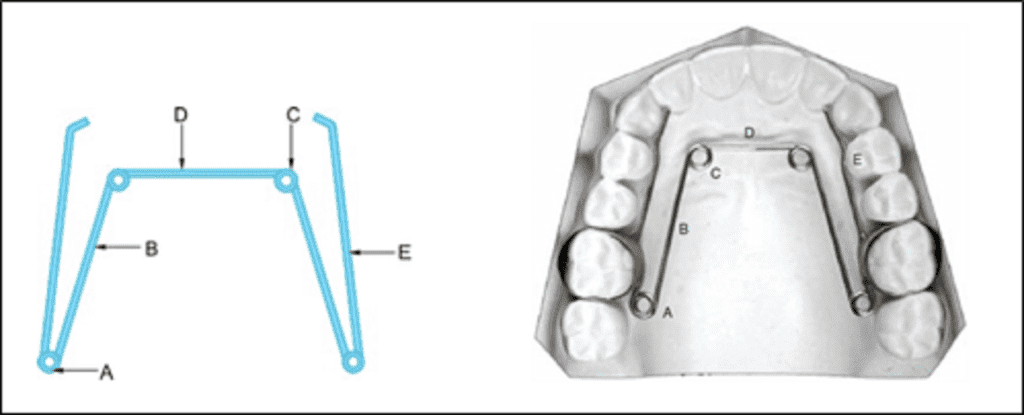

Quad/ Tri/Bi Helix appliance

Quad helix was introduced by Robert M Ricketts.

The appliance is a precursor to the tri- and the bi-helix appliances. They are all named after the number of helices incorporated in the appliance.

Appliance framework ̶ The quad helix consists of four helices made of 0.038″ diameter wire (elgiloy or stainless steel wire), soldered to the molar bands. The length of wire increases the range of action and flexibility, and decreases the force levels. The tri- and the bi-helix appliances incorporate only three and two helices respectively.

It is a fixed appliance comprising stainless steel bands cemented onto the maxillary first molars and a standard stainless steel arch attached to the palatal surfaces of the teeth.

Parts of quad helix: (A) posterior helix, (B) palatal bridge, (C) anterior helix, (D) anterior bridge and (E) outer arm.

The quad-helix consists of two anterior and two posterior helices. The portion of wire in between the two anterior helices is called the anterior bridge and that connecting the anterior helices and the posterior helices is called the palatal bridge. The free ends that are usually adapted close to the premolar teeth are called the outer arms. The outer arms are soldered to the molar bands. The posterior helix should not extend more than 2 mm distal to the first permanent molar.

Activation – The appliance is capable of producing differential expansion i.e. it can be activated to produce expansion levels in the premolar and molar regions.

It can be activated prior to cementation of the bands by stretching the molar bands apart or in the mouth with the use of three-prong pliers.

- In the anterior bridge: Results in expansion in the molar region

- In the palatal bridge: Derotation and expansion of molar on the same side and distalization of molar on the opposite side

- Outer arms are activated to expand canines and premolars

- Opening of posterior helix expands the buccal arm

An initial expansion of 8 mm will produce 14 oz of force. Average force is 200–400 g depending upon the amount of expansion or activation. The expansion of the steel arch (normally 10 mm before insertion) exerts a lateral force on the teeth, resulting in a predominant transverse dentoalveolar expansion of the maxillary arch. If necessary, the appliance can be reactivated after 6 weeks. Once inserted, the appliance is not dependent on patient compliance.

Indications of quad helix appliance

- Narrow upper arch that needs expansion, e.g. in crossbites

- Crowded, mixed or permanent dentition in which long range growth can be predicted and requires mild expansion as there is lack of space for the upper laterals

- Class II malocclusions where the upper arch needs effective widening and upper molars need distal rotation

- Class III malocclusions where the upper arch needs effective widening and advances with class III elastics

- Thumb sucking and tongue thrusting cases with their modifications

- Unilateral or bilateral cleft palate

Advantages

- It provides excellent expansion in cleft palate patients

- Expansion is smooth and controlled

- In young children, skeletal expansion can be achieved

- Anterior bridge with helices acts as reminder for habit breaking

For correction of unilateral posterior crossbite in mixed dentition, it has been proved that the Quad Helix appliance is superior to the expansion plate in terms of effectiveness and cost minimisation and is therefore the preferred method of treatment (Petrén et al., 2013).

Disadvantages

- One major disadvantage of this appliance is buccal tipping of molars during excessive activation. This can be prevented by torquing the roots buccally.